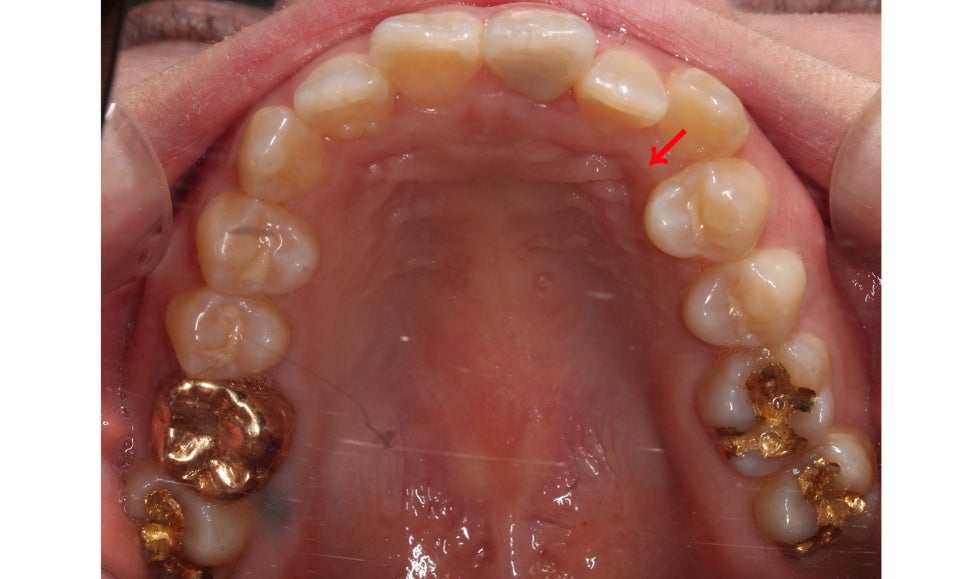

위의 구내사진을 보시면 사진에서

상악 우측 부분의 송곳니가

덧니처럼 맹출되어 있는 것을 확인할 수 있습니다.

송곳니교정 전 상악의 교합면을 보면

사진에서 좌측 송곳니가 입술 방향으로

뻐드러지게 나가 있는 모습을 확인할 수 있습니다.